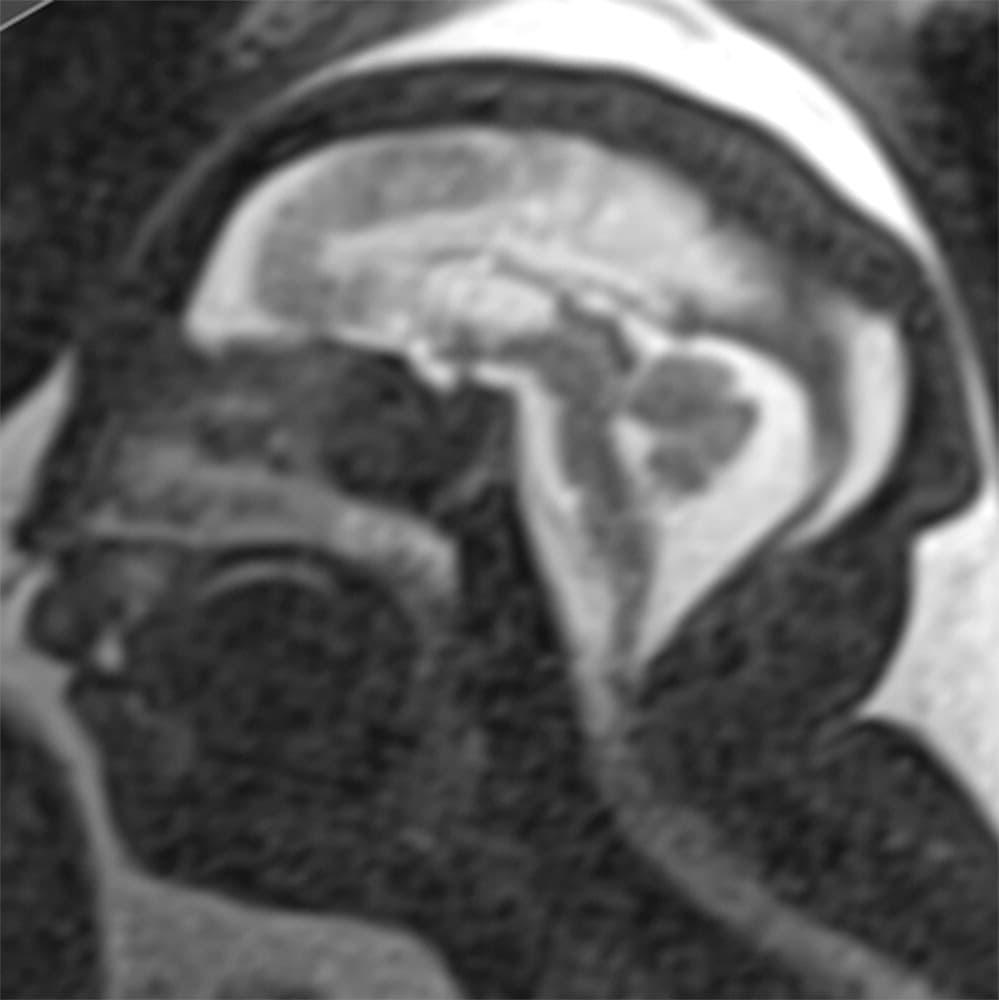

Investigadores brasileños difundieron este martes el mayor número hasta ahora disponible de imágenes computarizadas, resonancias magnéticas y ultrasonidos, de bebés y fetos infectados con el virus del Zika. El daño es mucho mayor del que anticipaban.

Así describe la radióloga brasileña Fernanda Tovar-Moll lo que vio al analizar centenares de imágenes computarizadas, resonancias magnéticas y ultrasonidos de 45 bebés que se contagiaron de zika en el vientre materno en el estado de Paraíba, en el noreste del país, donde el brote ha sido severo.

La mayoría nació con microcefalia, cuya característica más llamativa es que tienen el cerebro y la cabeza más pequeña. Pero muchos sufren una escala y severidad de daño mucho peor en partes importantes del cerebro como el cuerpo calloso, que conecta los dos hemisferios; el cerebelo, que juega un papel significativo en el movimiento, equilibrio y habla; y los ganglios basales, que controlan el pensamiento y la emoción.

Tovar-Moll es coautora de un estudio publicado el martes en la revista Radiology y fue liderado por la doctora Patricia Soares de Oliveira-Szejnfeld, a quien se le da crédito por establecer el vínculo entre el zika y la microcefalia en Brasil.